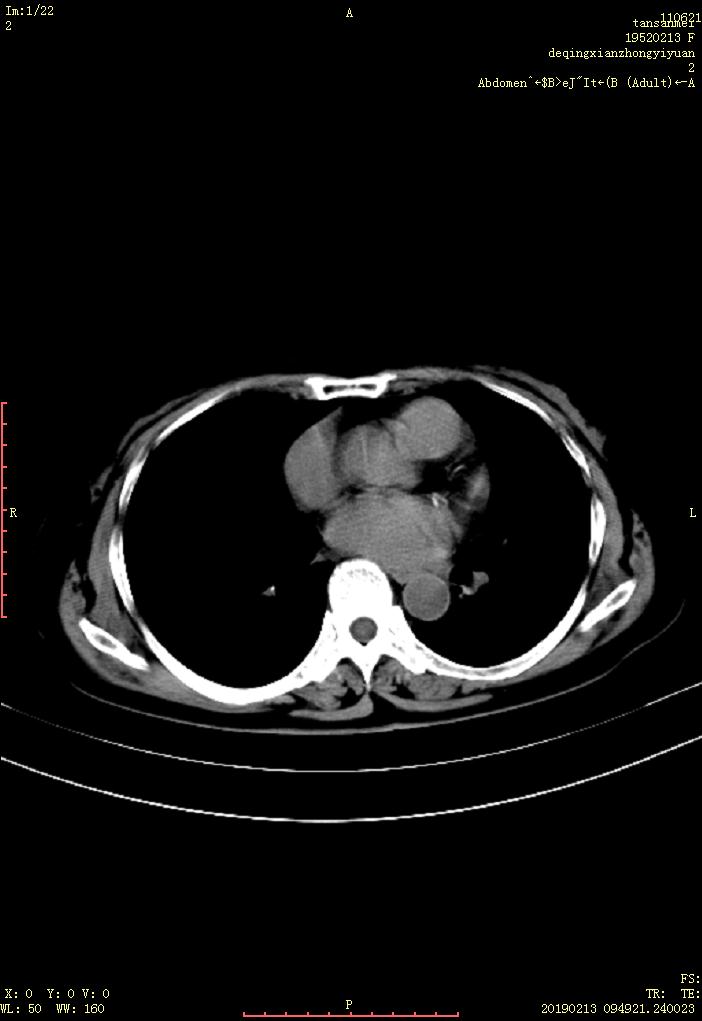

CT53510:B超显示肝S7区多发性稍高回声团。 ...

CT53510:B超显示肝S7区多发性稍高回声团。

病变位于6-7段,有两个重要表现。1,血管扩张2,肝脏非均匀性强化,肝内血管有三套,首先动脉期未见强化扩张血管,也未见门静脉提前显影,肝动脉扩张及肝动脉~门静脉短路可以排除。剩下只有肝静脉扩张了,特别是平衡期可以见到扩张更明显更扭曲,与右肝静脉走行,关系都很密切。所以考虑右肝静脉分支狭窄及扩张。布~加综合征。16排以上CT血管重建可以明确,楼主这机器好像是双排左右

的。

肝内血管稍扩张,肝右叶后段可见条结状低密度影,动脉期:结节显示清楚,病灶呈条片状强化,门脉期及延迟期。造影剂逐渐充填。其强化程度接近肝血管密度。胆囊内及右肾上极见斑点状高密度。右侧胸膜轻度增厚?考虑:肝右叶血管性病变----肝血管瘤?胆囊结石。右肾结石。